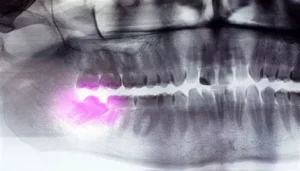

Impacted wisdom teeth are a common dental issue that many people face. These third molars, located at the back of the mouth, often emerge during